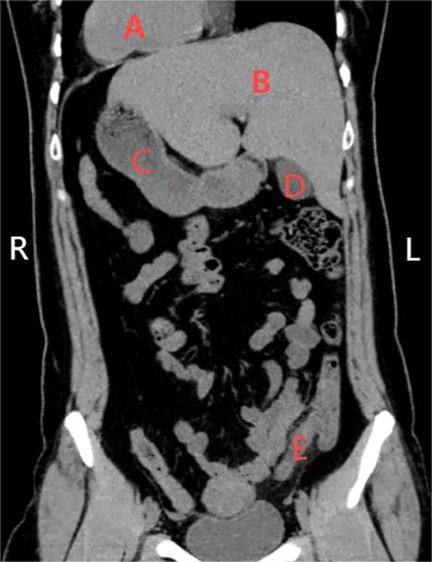

Background: Congenital visceral heterotaxy (CVH) is a rare congenital anomaly characterized by the abnormal arrangement (malposition) of thoracic and abdominal organs. This condition can significantly complicate surgical planning and intraoperative management, particularly when a history of prior abdominal surgery is present and laparoscopic intervention is required. The limited literature on managing such cases underscores the necessity for meticulous preoperative planning and intraoperative adaptability. Case Summary: A 42-year-old Chinese woman with congenital visceral heterotaxy and a history of cesarean section 11 years prior was admitted with acute suppurative appendicitis. Preoperative imaging, including ultrasound and CT, confirmed the diagnosis and revealed severe intra-abdominal adhesions. The patient underwent a laparoscopic appendectomy under general anesthesia. During the procedure, adhesions—likely stemming from the prior cesarean section—significantly impeded visualization and access to the appendix. Despite these challenges, the appendectomy was completed successfully without complications. The patient's postoperative recovery was uneventful, and she was discharged on the third postoperative day. Conclusion: This report highlights the successful management of a complex case involving a patient with both congenital visceral heterotaxy and severe intra-abdominal adhesions. It demonstrates that laparoscopic surgery is a feasible and safe option in such challenging scenarios, emphasizing the critical importance of meticulous preoperative planning, intraoperative adaptability, and a patient-tailored surgical approach. This case contributes to the sparse literature on laparoscopic surgery in patients with CVH and a history of abdominal surgery, offering valuable insights for surgeons facing similar complex presentations.